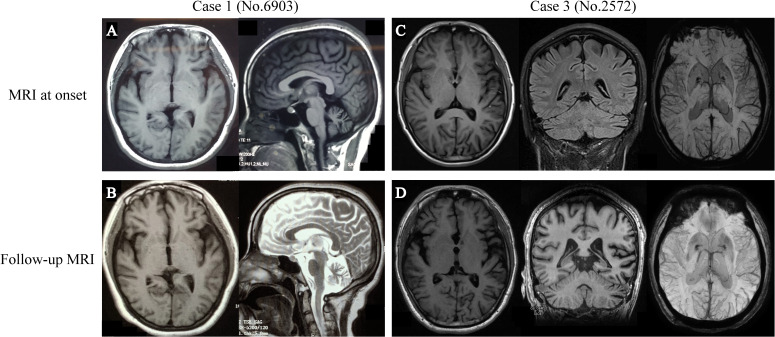

Results: Among the 14 patients in our cohort, 16 PLA2G6 variants were identified, including seven novel and nine previously reported variants. The mean age at symptom onset was 26.50±6.57 years. The most common initial presentation was parkinsonism (9/14, 64.3%), followed by gait disturbance (6/14, 42.9%) and psychiatric symptoms (1/14, 7.1%). A literature review identified 118 patients with PLA2G6-related parkinsonism, with a mean age at onset of 24.53±8.84 years. The most common initial clinical features included parkinsonism (61/117, 52.1%), cerebellar signs (46/85, 54.1%), cognitive impairment (65/92, 70.7%) and psychiatric symptoms (80/93, 86.0%). Subgroup analysis showed that the mean age at symptom onset was older in Chinese patients (26.65±7.08 years) compared with those of European ancestry (20.83±9.79 years) (p=0.016). Additionally, patients of European ancestry showed delayed parkinsonism 5.35±8.14 years after onset. Iron deposition was reported more frequently in patients of European ancestry (10/16, 62.5%) than that in Chinese patients (6/37, 16.2%) (p=0.0002).